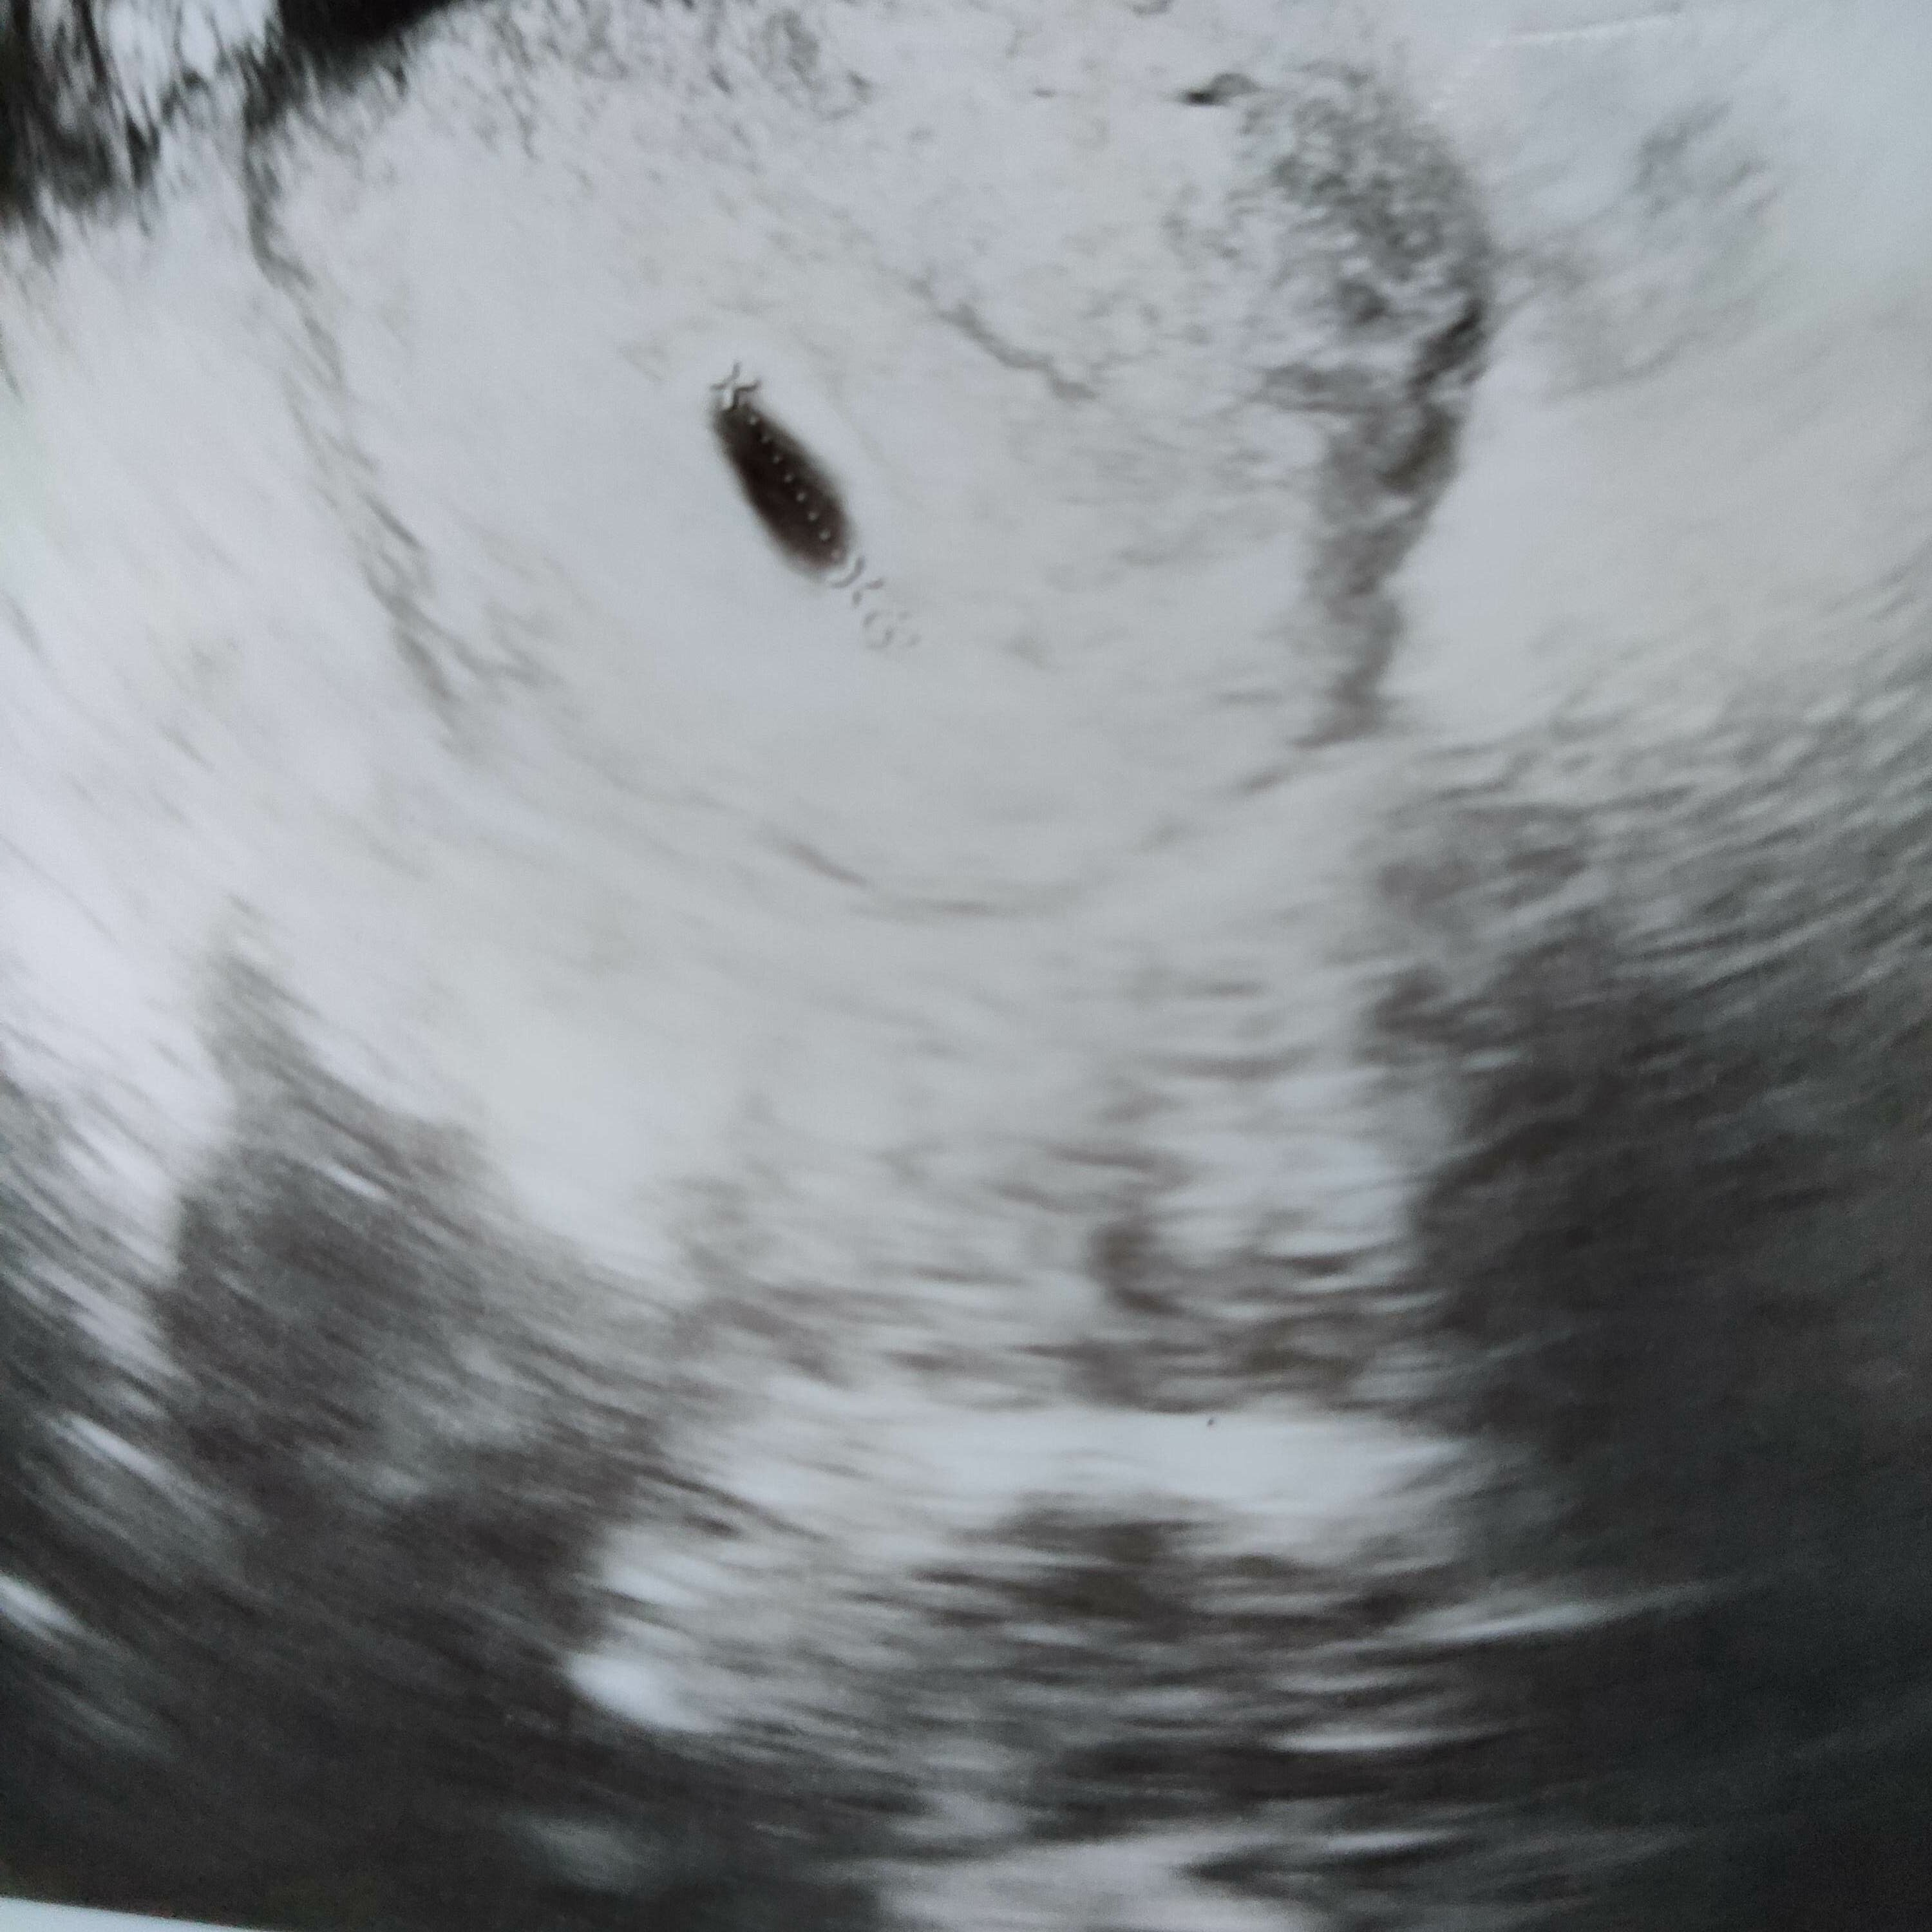

Hej dziewczyny u mnie niestety ostatecznie potwierdzono puste jajo płodowe więc do Was nie dołączę [emoji20]

Zobacz załącznik 1256789